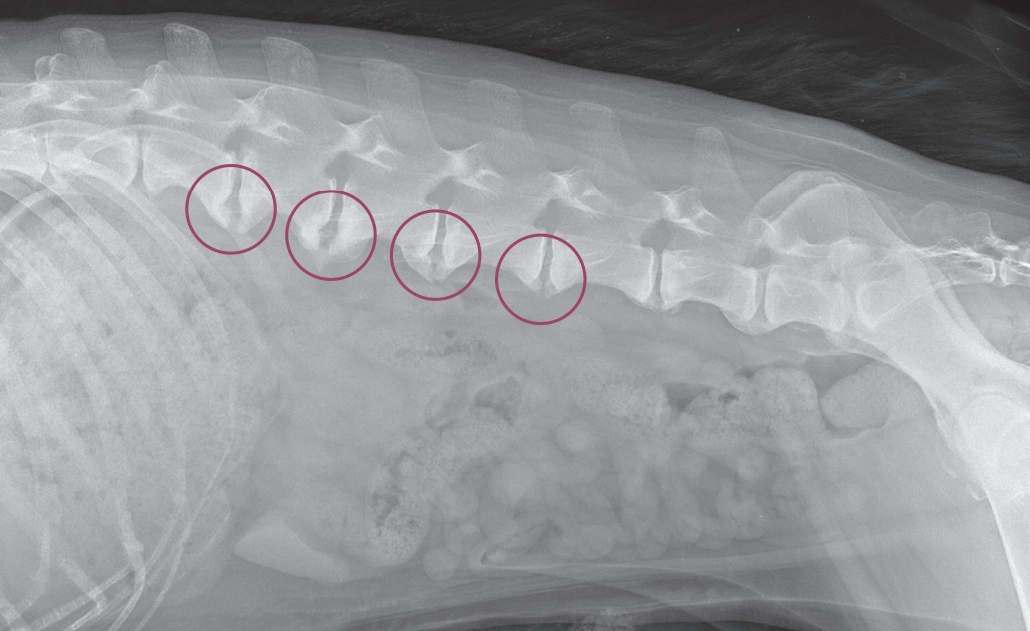

Spondylóza je degenerativní onemocnění páteře, které postihuje obratle a meziobratlové ploténky. Jedná se o nezánětlivou osteofytickou reakci meziobratlových prostorů páteře. U psů je spondylóza relativně běžná, zejména u starších jedinců a některých velkých plemen.